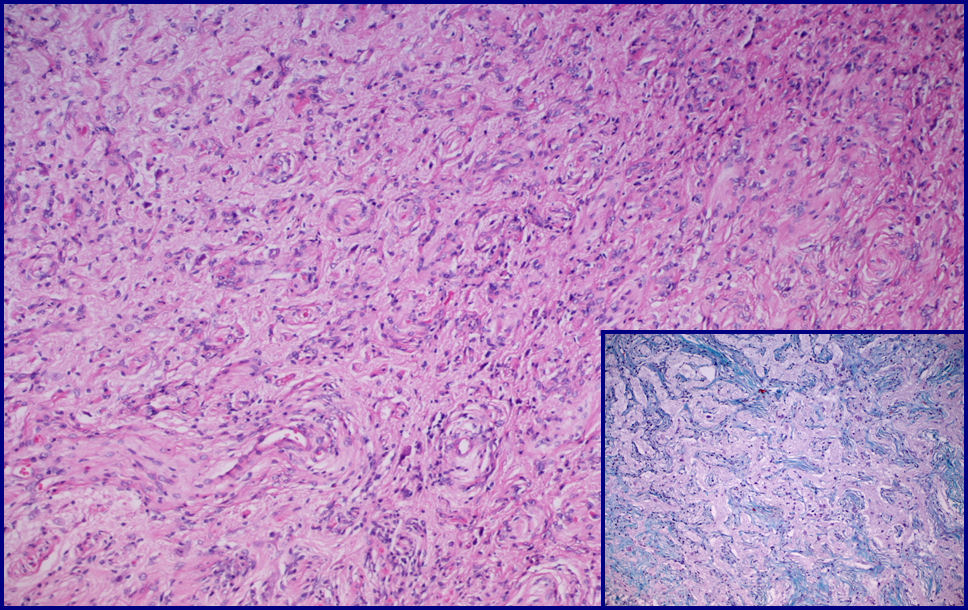

Fig. 5. Proliferación vascular rodeada de cels.meningoteliales que se extiende en el cortex cerebral, con distintos grados de fibrosis. H-Ex100, T. de Masson x 200 Fig. 6. Vasos de pequeño tamaño, con paredes hialinizadas rodeados concentricamente de cels. meningoteliales. El fondo está constituido por celularidad glioneuronal. H-Ex200